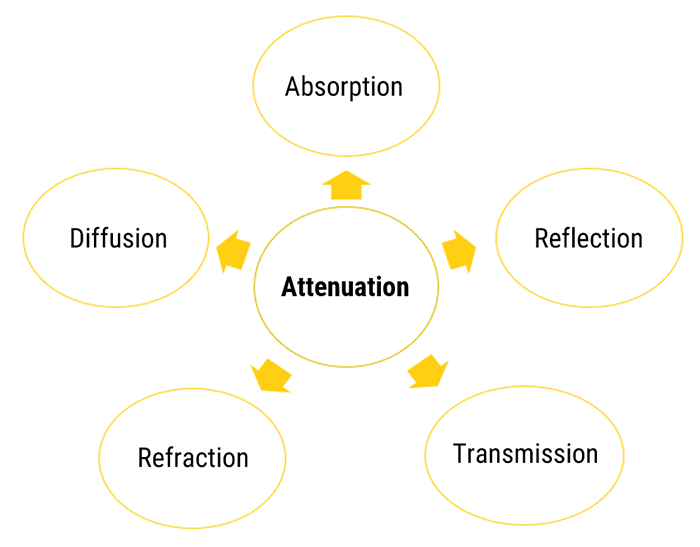

The sound energy is attenuated or weakened as it passes through the tissues. In fact, as the ultrasound wave travels through a medium, parts of it are reflected, scattered, absorbed or refracted.

Absorption

Reflection / Transmission

The Reflection of a sound wave occurs when the wave passes between two tissues of different acoustic speeds and a fraction of the wave ‘bounces’ back. Sound waves that are reflected directly to the transducer will lead to the vibration of the crystals, thus causing an electrical signal and creating the desired image. The equations of transmission and reflection of the ultrasonic intensity are independent of the frequency. Therefore, changing the transducer frequency does not change the transmitted or reflected intensity fraction at an interface. The three beams have the same direction.

Reflection / Refraction

Another phenomenon is the Refraction of a sound wave, which occurs when the wave travels between tissues with different propagation speeds. The refraction is defined by the change in the direction of the sound wave and is determined by Snell’s law. We can see how the direction of the wave has changed or deviated, as it passes through the interface.

Diffusion

In Conclusion, we can say that not all echoes will return back to the probe. Some of them are scattered in all directions, creating images with artifacts. This is specifically true for very small objects or rough surfaces.